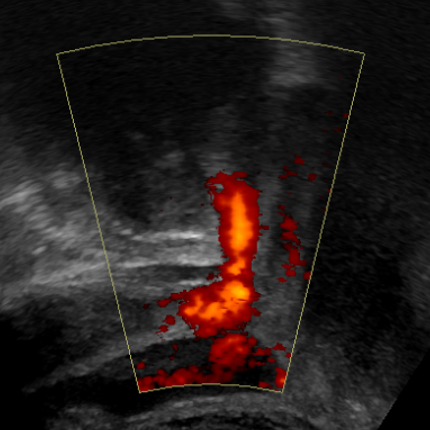

See the HIFU beam profile and the focal point with ultrasound

The beam profile of the HIFU is rendered while the HIFU transducer runs at “Low-Power” mode, below the threshold for tissue damage. Only after getting the focal point on target, the mode of operation can be switched to “High-Power”, in order to generate the therapeutic effect.

Imaging of the HIFU beam profile is executed at a high frame-rate, resulting in a real-time display of the actual HIFU scene behind the transducer; therefore, the location of the focal point in the body, as well as the occurrence of unwanted, secondary hot spots can be identified and addressed online.

Implementing our pioneering holistic approach for ultrasound sequencing, the HIFU and the imaging fields are synchronized and processed together. The result is an interleaved display of the ‘regular’ ultrasound in gray level mode, combined with the HIFU beam profile rendered in colors on the same screen.